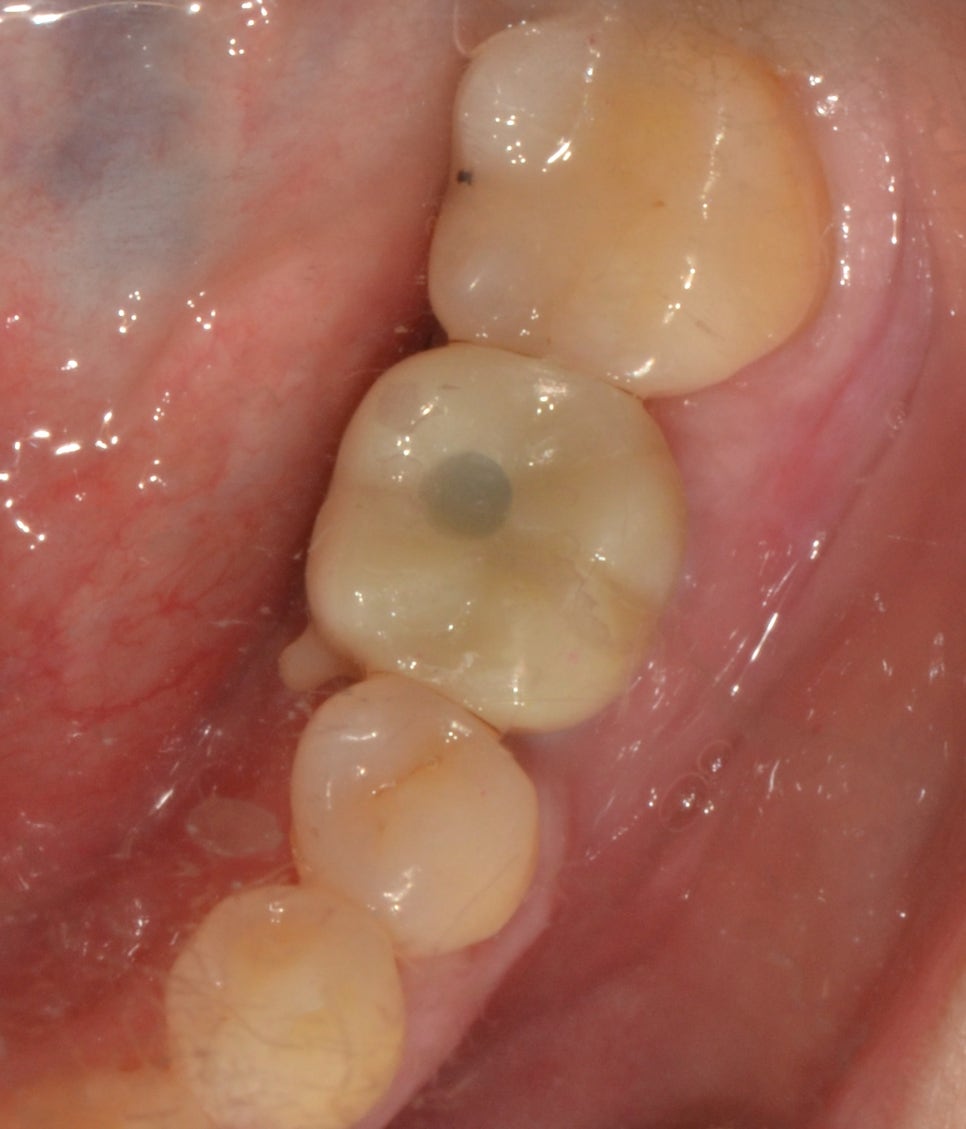

치료 전

40대 여성분이었으며 상실된 치아가 있으셨고 해당 부분을 3D CT로 정밀하게 확인해 보니 잇몸뼈의 양도 부족한 상태였습니다. 위에서 설명드린 것과 같이 방치를 오래 하게 되면 잇몸뼈의 양과 상태가 좋지 않을 수 있다고 말씀드렸는데요. 뼈의 양이 충분하지 않다면 바로 임플란트 식립이 어렵습니다. 그 이유는 고정이 잘 되도록 지지를 해주는 것이 잇몸뼈였는데요. 충분하지 않은 상태로 만약 시술이 이뤄진다고 하더라도 고정이 잘되지 않아 흔들릴 수 있었죠. 그래서 임플란트 치료와 함께 골이식을 동반하는 것을 말씀드리며 치료를 진행했습니다.

치료 후

좌측 제1대구치 골이식을 동반한 임플란트 시술을 하고 난 후 보철로 마무리해주었습니다. 식립이 끝난 후에는 잇몸 관리도 같이 해드렸습니다. 상실된 치아를 임플란트로 잘 해결해 주었으니 이제는 밥을 먹는 것도 편안하게 잘 먹을 수 있을 것 같다고 말씀해 주시면서 환자분도 만족스러워하셨습니다.